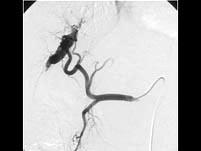

问题 微小肝癌主要通过哪项检查确定()

选项 A.AFP测定 B.B超检查 C.选择性肝动脉造影 D.放射性放射性核素肝扫描 E.MRI检查

答案 C